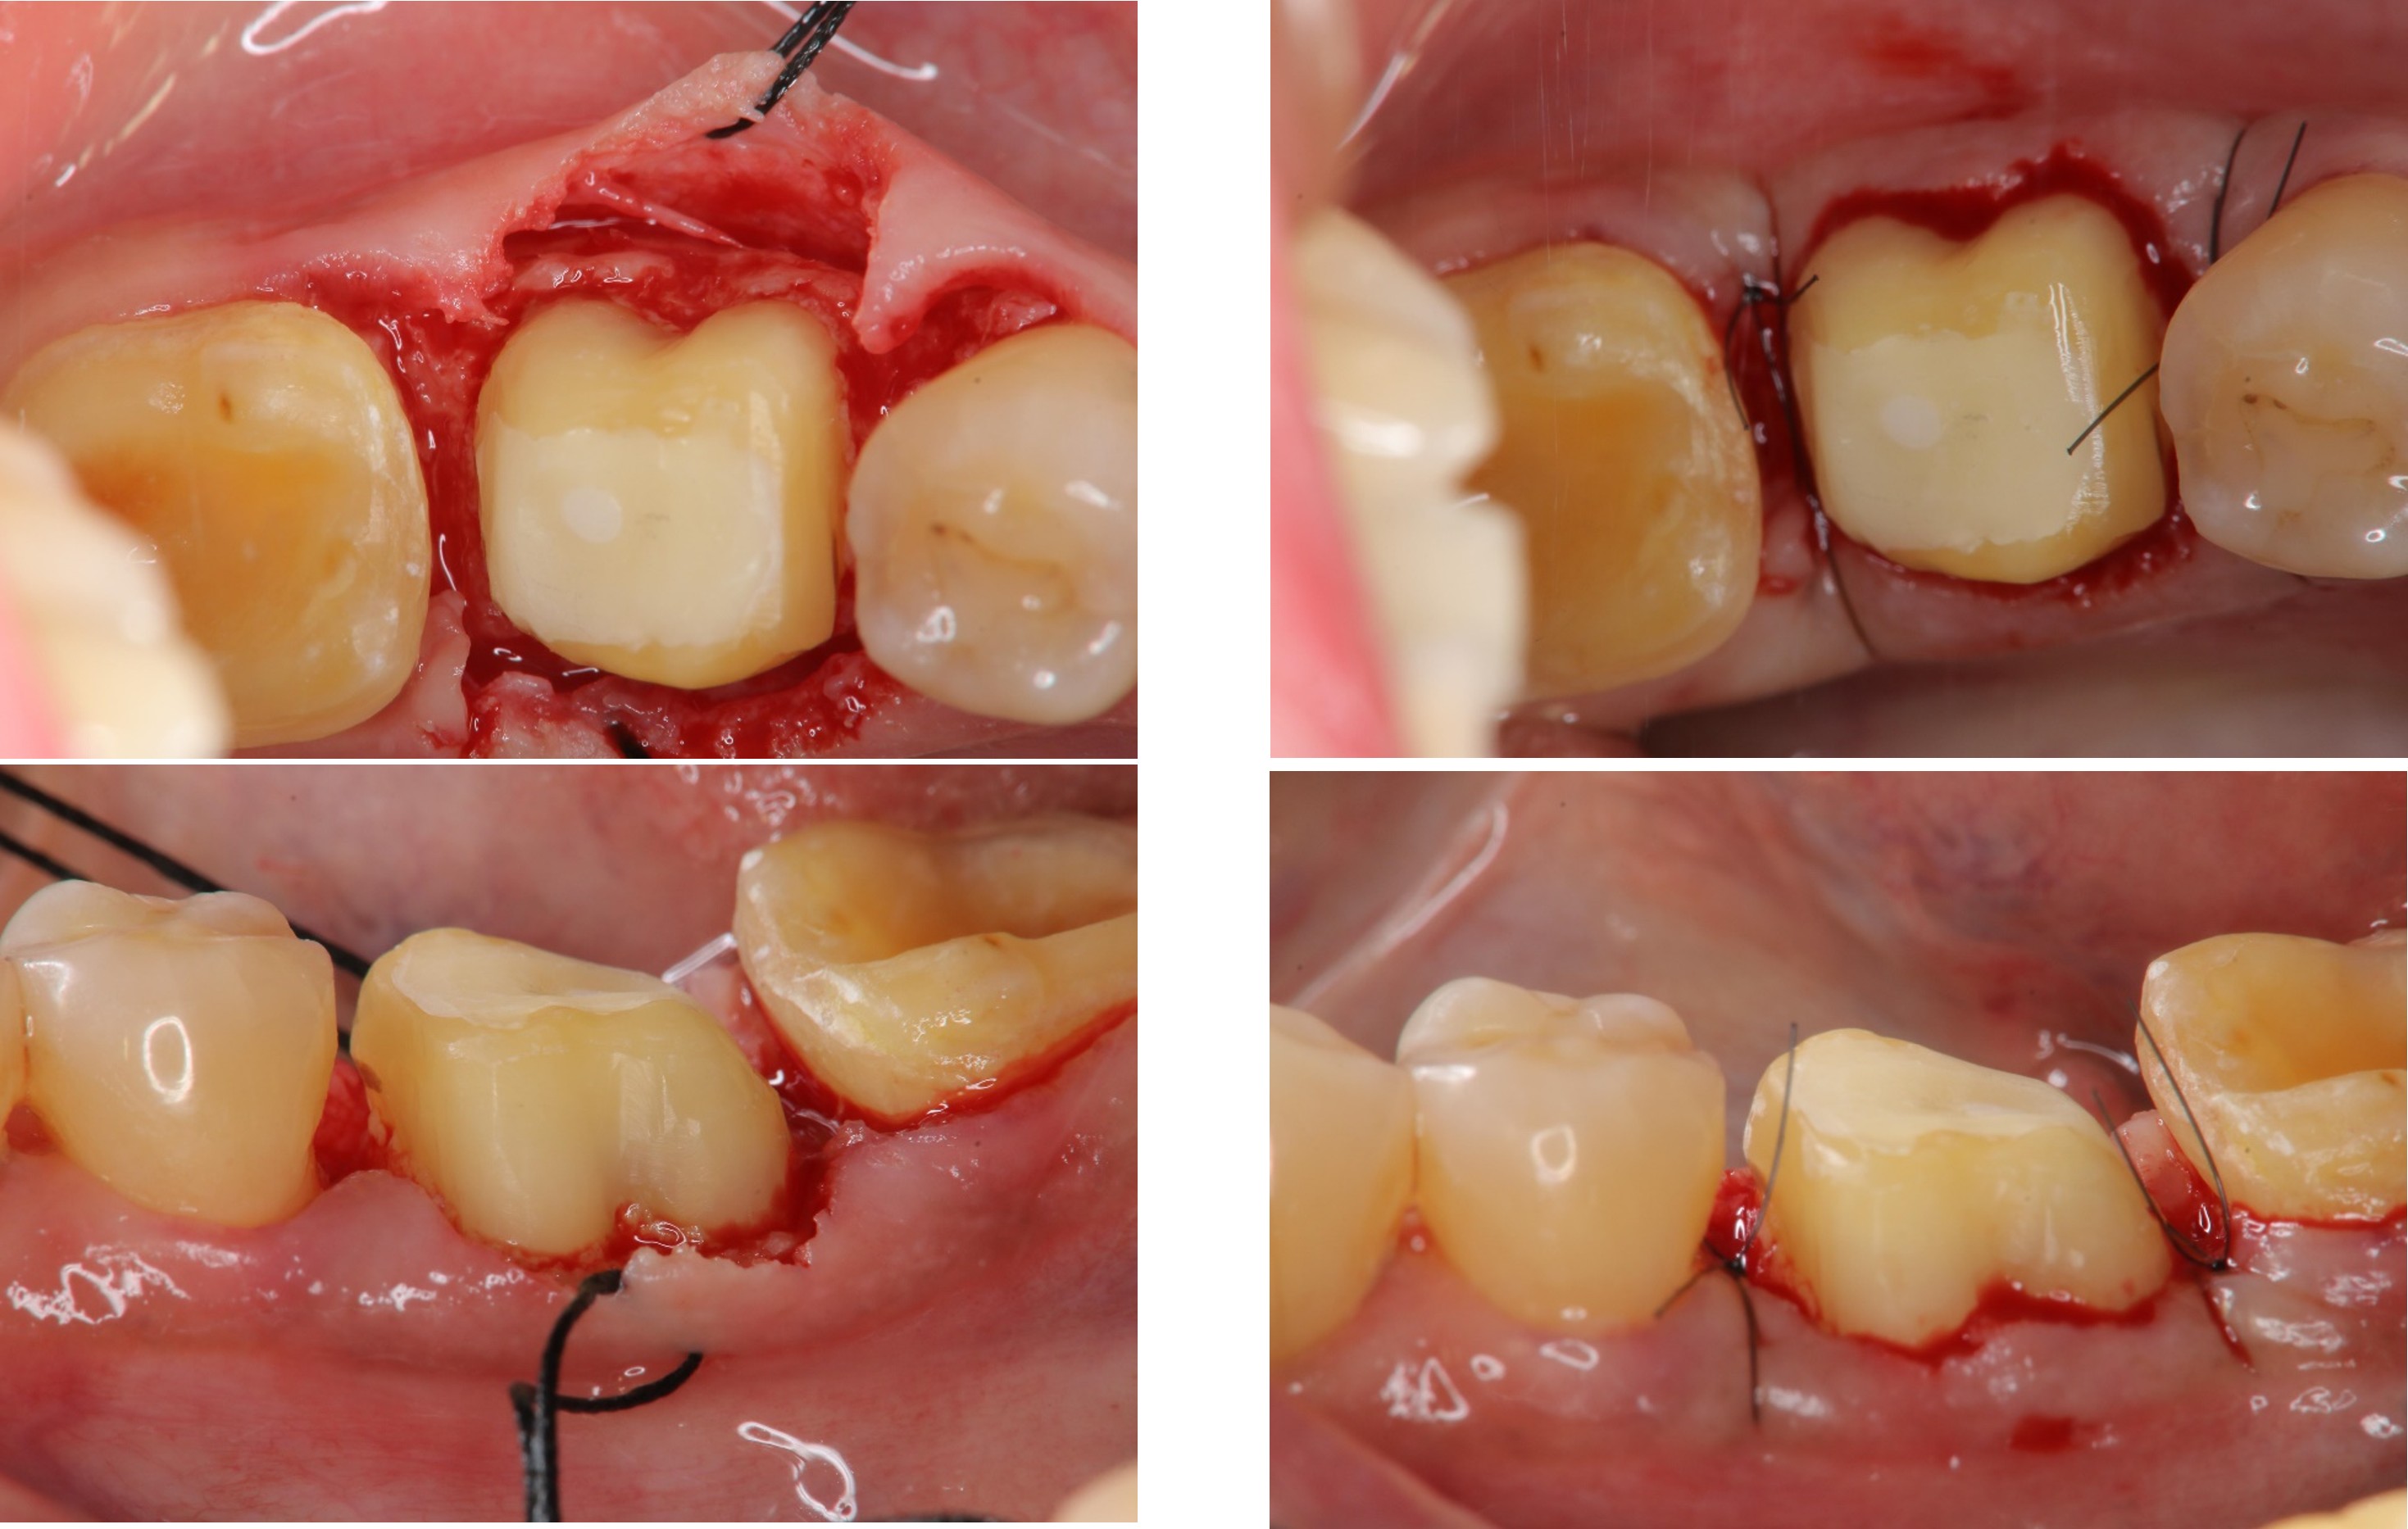

牙冠增長手術-#36

牙冠增長手術-#37